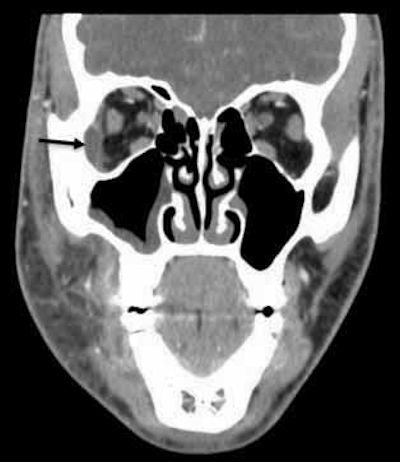

In addition, a CT scan taken at the outside hospital was reviewed by medical center clinicians. They identified a subperiosteal abscess at the right lateral orbit. The right canine space abscess came from the buccal roots of tooth #3. Also, the scan showed that fluid collected at the right canine space superiorly and posteriorly to the right lateral orbit, and right maxillary sinusitis was present.